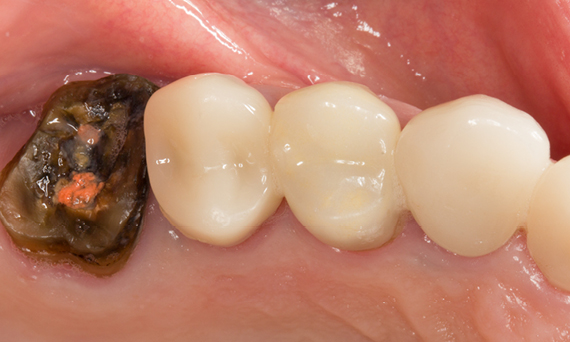

Before: A large carious mesial lesion on tooth 15. The tooth showed asymptomatic apical periodontitis and a significant loss of tooth structure.

After: Chairside-fabricated restoration made of CEREC MTL Zirconia designed using the Biogeneric individual function in the CEREC Software.